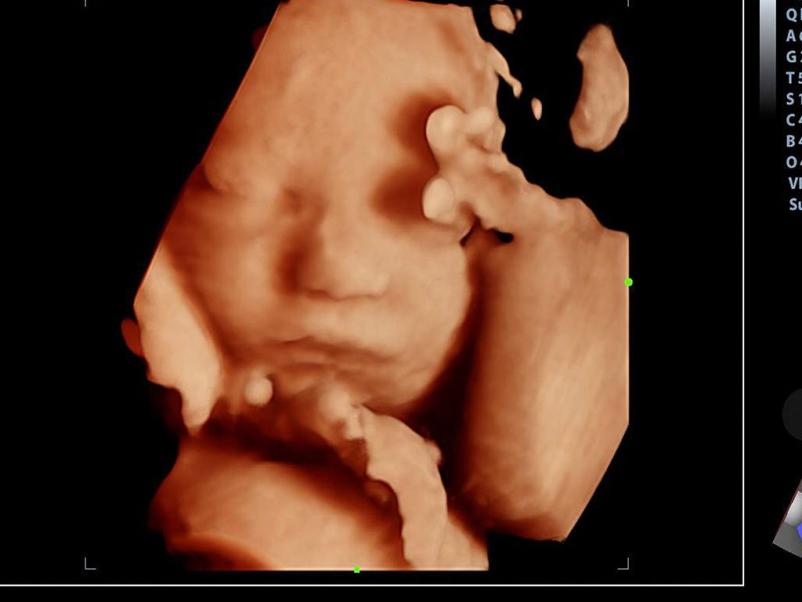

Znani smo po celoviti, profesionalni specialistični obravnavi naših pacientk, katerim so na voljo ginekološke, porodniške in druge ambulantne storitve, vključno z ultrazvokom in merjenjem nuhalne svetline, ki jih opravljamo diskretno in tako, da so za pacientke kar najmanj neprijetne.